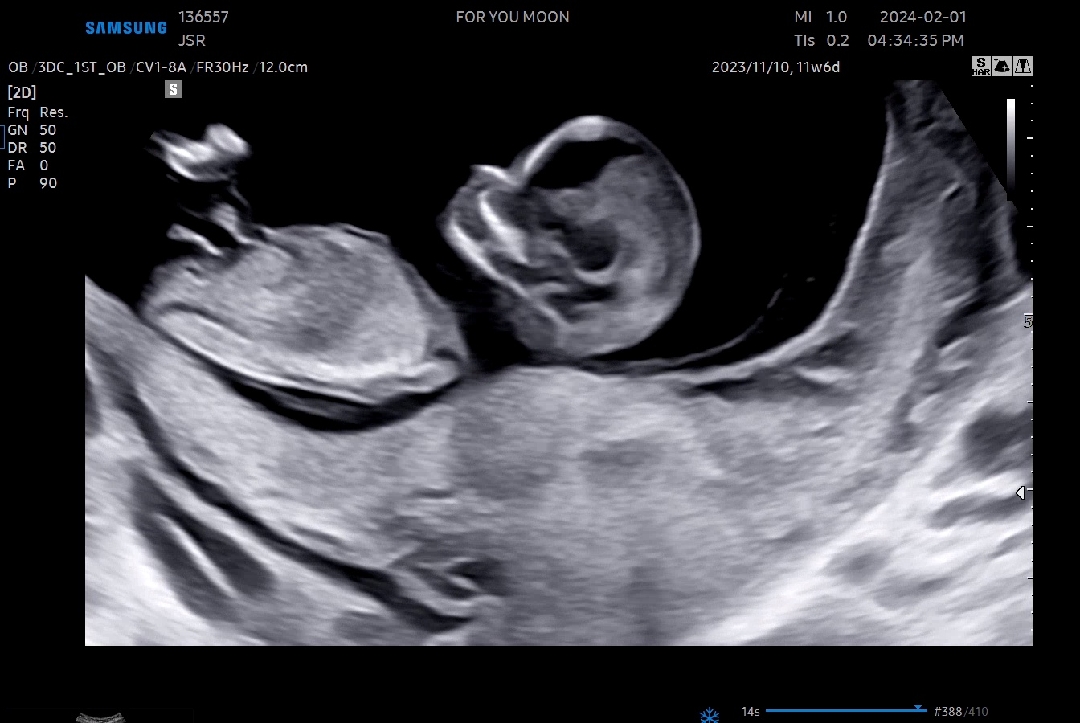

제 초음파보고 의견이 분분했는데 고수분들?은 아들의견 쥬시더라구요 각도는 아들같긴한데 아들도 끝갈라짐이잇나요?! 아들 같아 보이시나용?